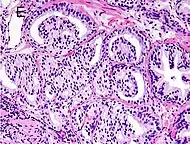

Cribriform pattern: Gleason grade 4

Gleason 4

Gleason pattern 4 glands are no longer single/separated glands like those seen in patterns 1-3. They look fused together, difficult to distinguish, with rare lumen formation vs Gleason 1-3 which usually all have open lumens (spaces) within the glands, or can be cribriform-(resembling the cribriform plate/similar to a sieve: an item with many perforations). Fused glands are chains, nests, or groups of glands that are no longer entirely separated by stroma-(connective tissue that normally separates individual glands in this case). Fused glands contain occasional stroma giving the appearance of "partial" separation of the glands. Due to this partial separation, fused glands sometimes have a scalloped (think looking at a slice of bread with bite taken out of it) appearance at their edges.[4][7]